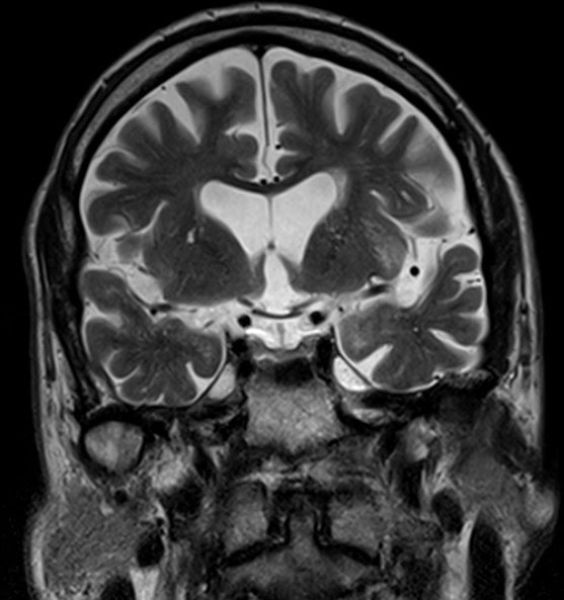

Хроническая ишемия головного мозга и лейкоареоз: симптомы и лечение